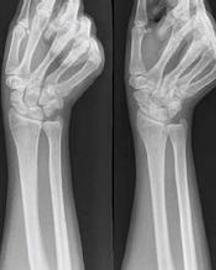

舟骨骨折是一种常见的骨折,多是因间接暴力造成的,发生舟骨骨折后,严重的影响了患者日常生活和工作,应及时治疗。舟骨是腕关节的一块小骨头。舟骨靠近排桡侧,其状如舟,故其名。但不规则,背面狭长,粗糙不平,与桡骨形成关节。跌倒受伤时,掌心着地,舟骨首当其冲,受压于桡骨与头状骨之间,形成骨折。由于舟骨所处位置剪力大,血运不良,故难于愈合。